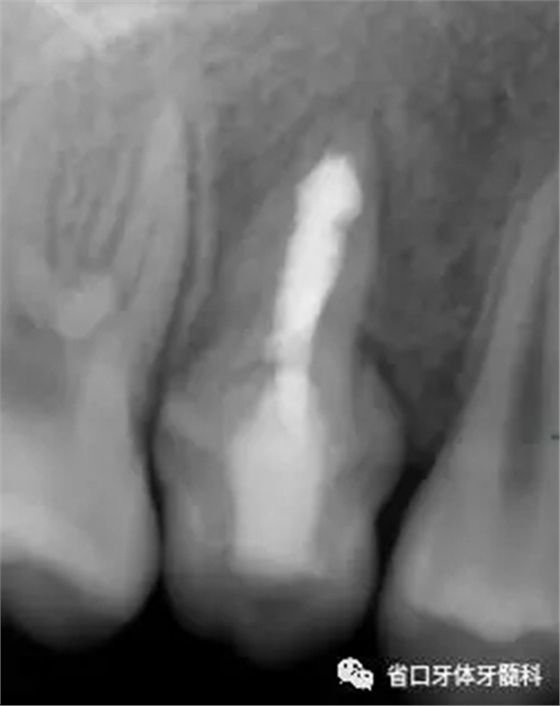

圖5 根管內(nèi)封vitapex